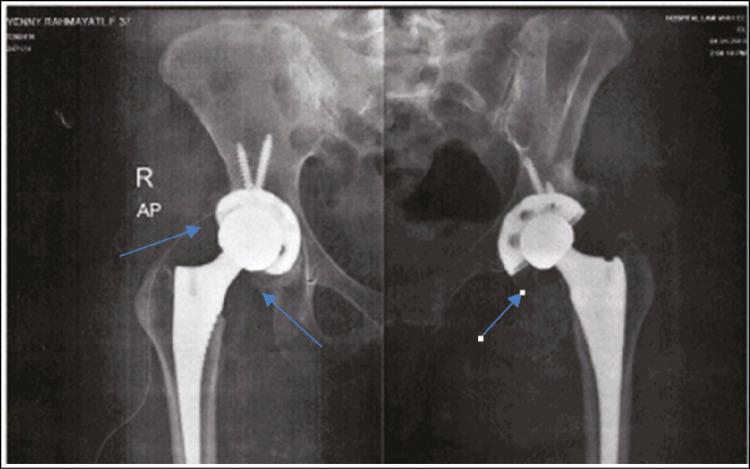

应用红外热成像技术对系统性红斑狼疮患者颞下颌关节周围肌肉区域热状况的研究:一例报告

Thermal Condition of Muscle Area Around the Temporomandibular Joint in Patient with Systemic Lupus Erythematosus Using Infrared Thermography Application: A Case Report.

Recently, the use of infrared thermography in medical has been increasingly developed and widely used in medical devices to detect diseases, including one used in the field of dentistry, which can be used to detect joint conditions in case of temporomandibular disorder (TMD). Some literature has shown this method of infrared thermography was used to determine the surface temperature of the skin based on the emission of infrared radiation from the body. Thermal measurement is also a noninvasive method that does not provide patient inconvenience, but its application until now has not been so wide. The case study reported on the description of thermal condition of muscle area around temporomandibular joint (TMJ) in a 42-year-old woman with systemic lupus erythematosus (SLE) disease. She had experienced TMD. Infrared thermography is applied to observe the thermal condition of the muscle area around the right and left joints by thermal detection. Thermal measurement was obtained on infrared image capture, and the temperature difference was found to be greater than 0.3°C. Several studies have shown that temperature in the area around TMJ was higher, and thermal asymmetry was greater in individuals with joint disorder/TMD when compared with normal groups.

近年来,红外热成像技术在医学领域的应用得到了越来越多的发展,并广泛应用于医疗设备中以检测疾病,包括牙科领域使用的一种设备,它可用于在颞下颌关节紊乱(TMD)的情况下检测关节状况。一些文献表明,这种红外热成像方法是基于人体发出的红外辐射来测定皮肤表面温度的。热测量也是一种非侵入性方法,不会给患者带来不便,但到目前为止其应用还不够广泛。该病例研究报告了一名患有系统性红斑狼疮(SLE)疾病的42岁女性颞下颌关节(TMJ)周围肌肉区域的热状况描述。她曾患有颞下颌关节紊乱症。通过热检测应用红外热成像技术观察左右关节周围肌肉区域的热状况。在红外图像捕捉时进行热测量,发现温差大于0.3°C。几项研究表明,与正常组相比,关节紊乱/颞下颌关节紊乱症患者的颞下颌关节周围区域温度更高,热不对称性更大。